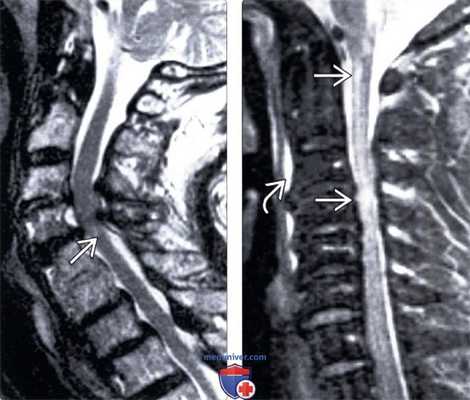

(Слева) Т2-ВИ, сагиттальная проекция: признаки многоуровневого дегенеративного поражения шейного отдела позвоночника. На уровнях С3-С4 и С4-С5 отмечается выраженный стеноз спинномозгового канала за счет протрузий межпозвонковых дисков, спондилофитов замыкательных пластинок тел позвонков и гипертрофии дорзальных связок. После травмы у данного пациента развилась клиника центрального спинномозгового синдрома, свидетельством чего является небольшой гиперинтенсивный очаг в зоне повреждения спинного мозга на уровне С4-С5.

(Справа) На сагиттальном STIR МР-И пациента с травмой шейного отдела позвоночника видны признаки врожденного стеноза спинномозгового канала и минимально выраженных дегенеративных изменений. На уровне цервикомедуллярного перехода и С4 отмечается патологическое усиление Т2-сигнала спинного мозга, свидетельствующее о его повреждении. Обратите внимание на гиперинтенсивность сигнала превертебральных мягких тканей (гиперэкстензионное повреждение).